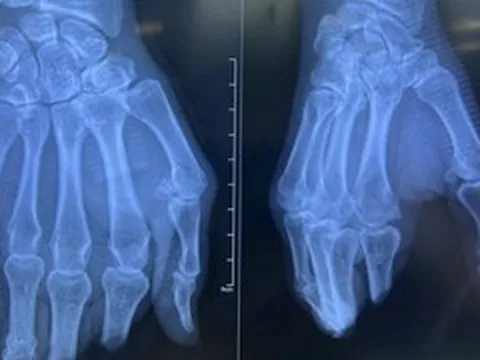

Bàn tay đứt lìa của mẹ bầu được nối lại sau thời gian 'nuôi' ở chân 1

Sau hơn 2 tháng được ê-kíp bác sĩ “nuôi tạm” ở cẳng chân để bảo tồn mô và mạch máu, bàn tay bị đứt lìa của sản phụ mang song thai được nối trở lại vào tay.